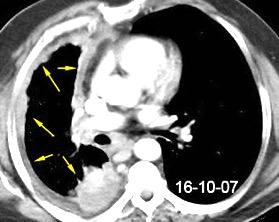

Tromboembolismo pulmonar.

Frecuencia del derrame:

Rx: 32%. TC: 47%

Unilateral. 85%

< 1/3 del hemitórax: 90%

Todos exudados

58% con eritrocitos

21% tabicación lo que causa demora en el diagnóstico

TEP. Empiema pleural. Atelectasia redonda

Porcel JM et al. Analysis of pleural effusions in acute pulmonary embolism: radiological and pleural fluid data from 230 patients. Respirology 2007/ Iguchi T et al. Desquamation of the subpleural lung parenchyma caused by empyema after pulmonary embolism: A case report. Respirol Case Rep. 2022 .